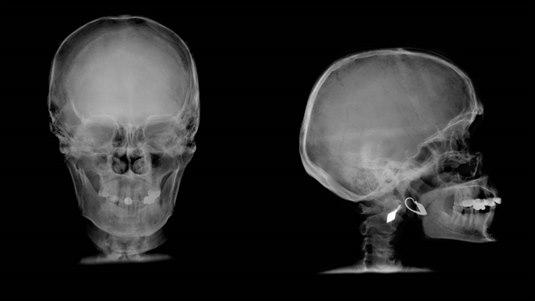

Hjernerystelse brukes dersom et støt mot hodet gir midlertidig påvirkning av hjernefunksjonen, typisk et kortvarig bevissthetstap, ofte ledsaget av forbigående hukommelsestap. Ved hjernerystelse er det ingen påvisbar skade eller blødning i hjernen ved bildeundersøkelser.

En hjernerystelse er en "rystelse" av hjernen, støtet mot hodeskallen får hjernen til å bevege seg inne i kraniet. Vanlige årsaker til hjernerystelse er sportsaktiviteter, fall, vold, og trafikkulykker. Noen besvimer, andre ikke. I de fleste tilfellene er bevisstløsheten kortvarig, vanligvis mellom noen få sekunder og opptil 30 minutter.